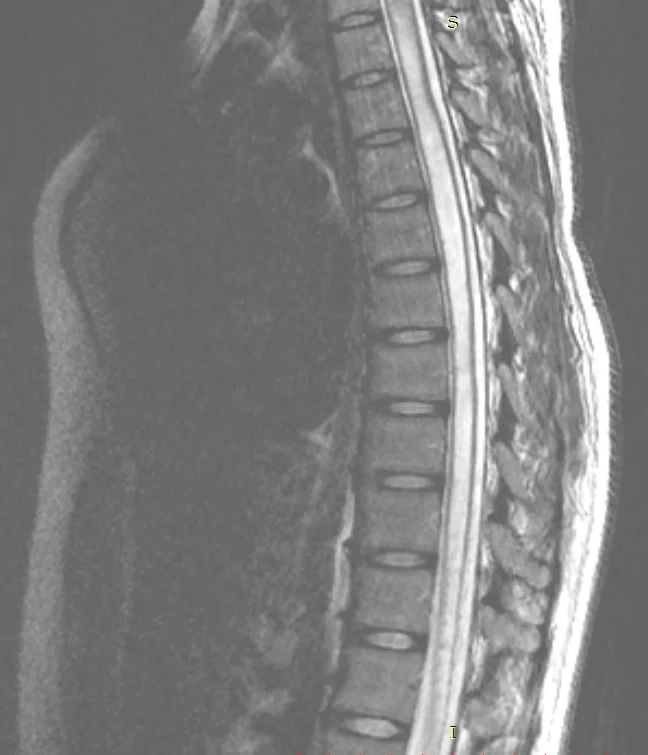

Νεαρή ασθενής 17 ετών με εκτεταμένη συριγγομυελία από την αυχενοπρομηκική συμβολή έως το τελικό τμήμα του νωτιαίου μυελού, λόγω συνδρόμου Chiari. Κλινικά αιμωδίες (μουδιάσματα) άνω άκρων, ζάλη.

Η μαγνητική τομογραφία περίπου 3 μήνες μετά το χειρουργείο δείχνει οτι οι αμυγδαλές της παρεγκεφαλίδας δεν καταδύονται πλέον πέραν του ινιακού τρήματος και -το κυριότερο- η συριγγομυελία έχει υποχωρήσει σημαντικά.